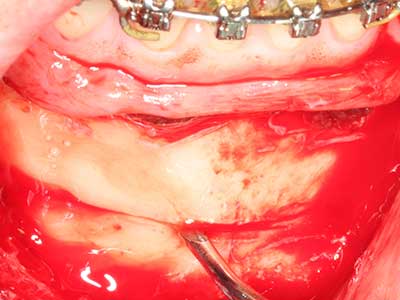

El tejido óseo no solo tiene un contenido puramente mineral, sino que también presenta una importante proporción de fibras de colágeno. Esto no solo garantiza una buena resistencia a la presión, sino también una cierta flexibilidad, que puede aprovecharse para la realización de aumentos. En la plastia de expansión clásica a efectos de una partición ósea, la cresta maxilar atrofiada se divide en su eje longitudinal y, tras alcanzar una profundidad de osteotomía suficiente, se extiende con cuidado (fig. 13-16), en un caso ideal sin desperiostizar de forma visible el maxilar (Brugnami, Caiazzo et al. 2014, Stricker, Fleiner et al. 2014). Los sistemas de tornillos y placas con distancia de expansión creciente han demostrado su eficacia para distanciar entre sí las dos tablas óseas por debajo del umbral de rotura. Por regla general, se requieren anchuras de hueso residual de al menos 3 a 4 mm (Chiapasco, Zaniboni et al. 2006) para garantizar una flexibilidad y una cobertura ósea suficientes de los implantes que van a incorporarse. En caso necesario, una osteotomía de descarga vertical unilateral o bilateral puede mejorar la flexibilidad. Como alternativa a la técnica clásica se ha descrito una combinación con otras técnicas de aumento, sobre todo en la parte bucal.

Con el uso de sierras piezoeléctricas la división se efectúa de forma especialmente cuidadosa y sin pérdidas importantes de las dimensiones, por lo que no se han encontrado diferencias significativas entre los implantes realizados en el maxilar dividido y en la cresta alveolar no deficitaria (Chiapasco, Zaniboni et al. 2006, Danza, Guidi et al. 2009). No obstante, precisamente en la partición profunda y limitada de forma local, es preciso asegurarse de que exista una adecuada irrigación por agua para evitar que se produzcan sobrecargas térmicas en las áreas de osteotomía apical.